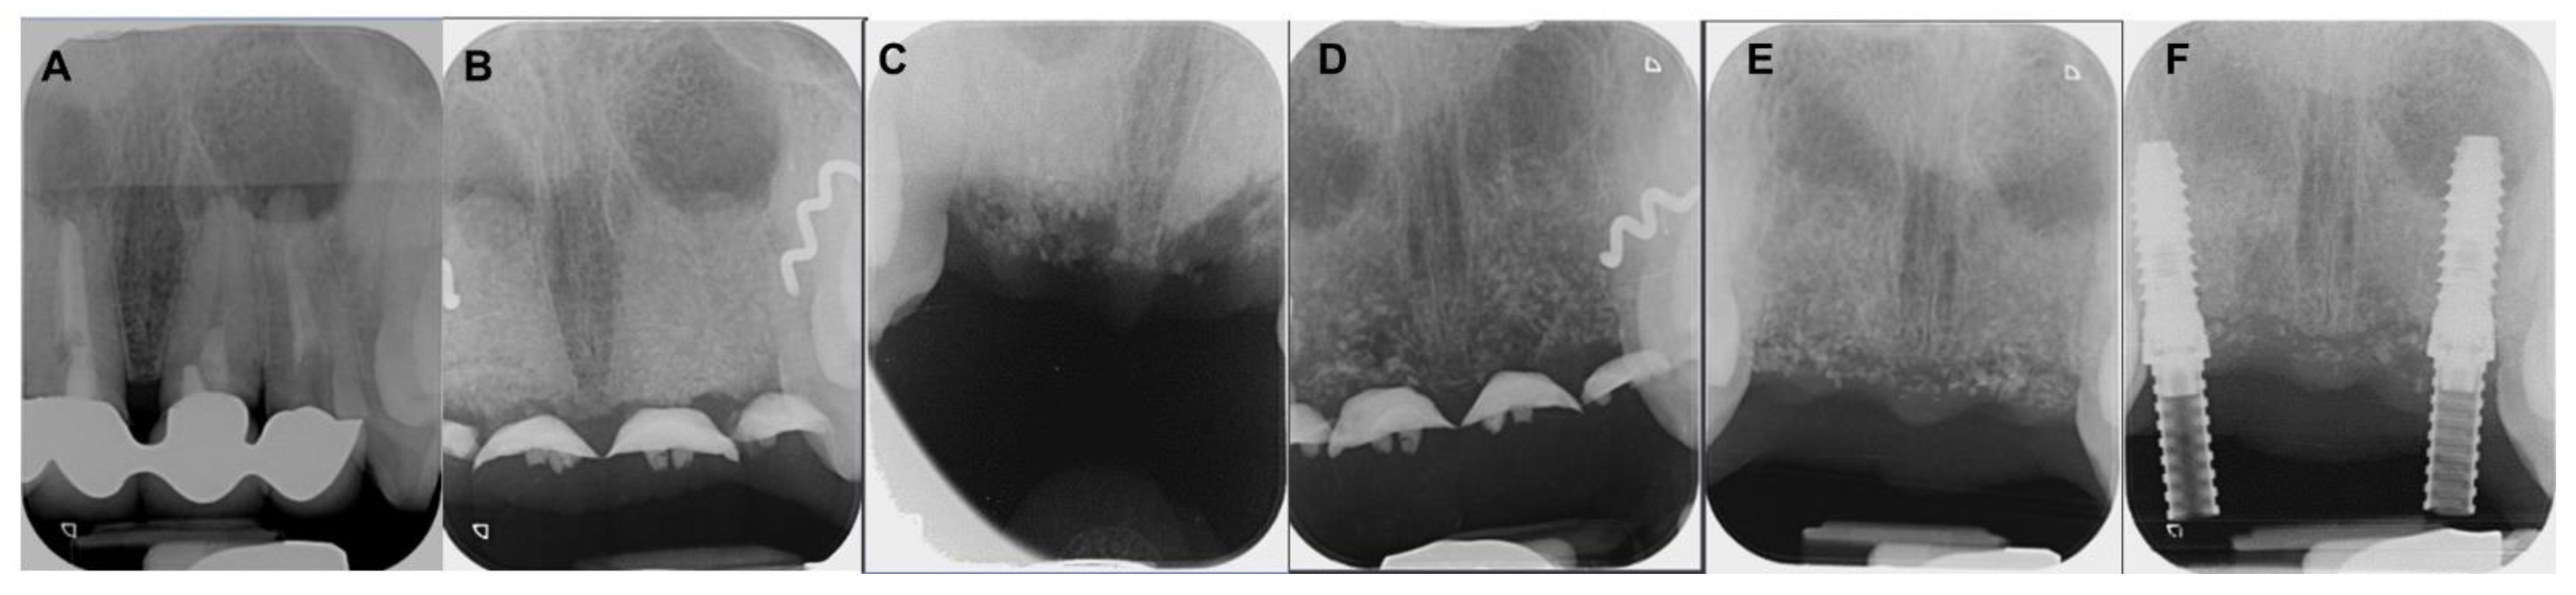

4.1. Patient No. 1

4.2. Patient No. 2

4.3. Patient No. 3

4.4. Patient No.4

4.5. Patient No.5

4.6. Patient No.6